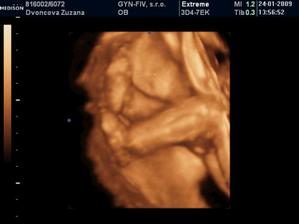

24.1.2009 nám pán doktor prezradil na 3D, že čakáme chlapčeka :o) ....po dlhom rozhodovani sme si povedali, ze to bude maly Nicolas...uz sa velmi tesime, ked pride na svet...caka ho tu cela velka rodina, ktora ho uz teraz velmi lubi :o))